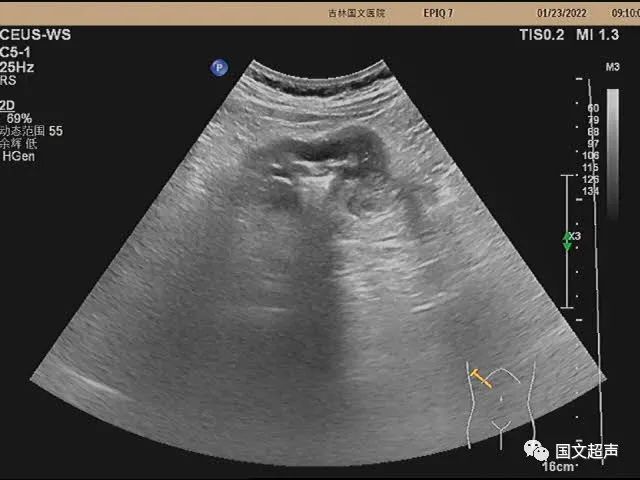

超聲檢查:右側(cè)結(jié)腸肝曲處腸壁不均勻性增厚,走行僵直,蠕動不佳,呈“假腎征”,術后病理:右側(cè)結(jié)腸低分化腺癌。